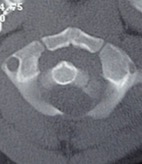

Instrumentación cervical en pacientes menores de 10 años. [Cervical Instrumentation and Fusion in Children Under 10 Years Old.]